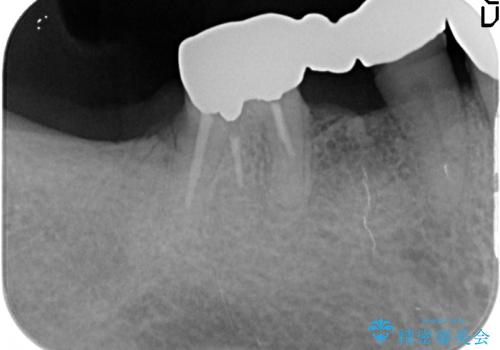

- 「歯がぐらぐらして噛めない、歯を抜いて欲しい、またしっかりと噛めるようになりたい。」、と歯周病治療を希望され来院されました。

歯の根本まで骨吸収が進み、ぐらぐらになってしまった歯を抜去し骨の造成を行ったのちインプラント治療を計画します。